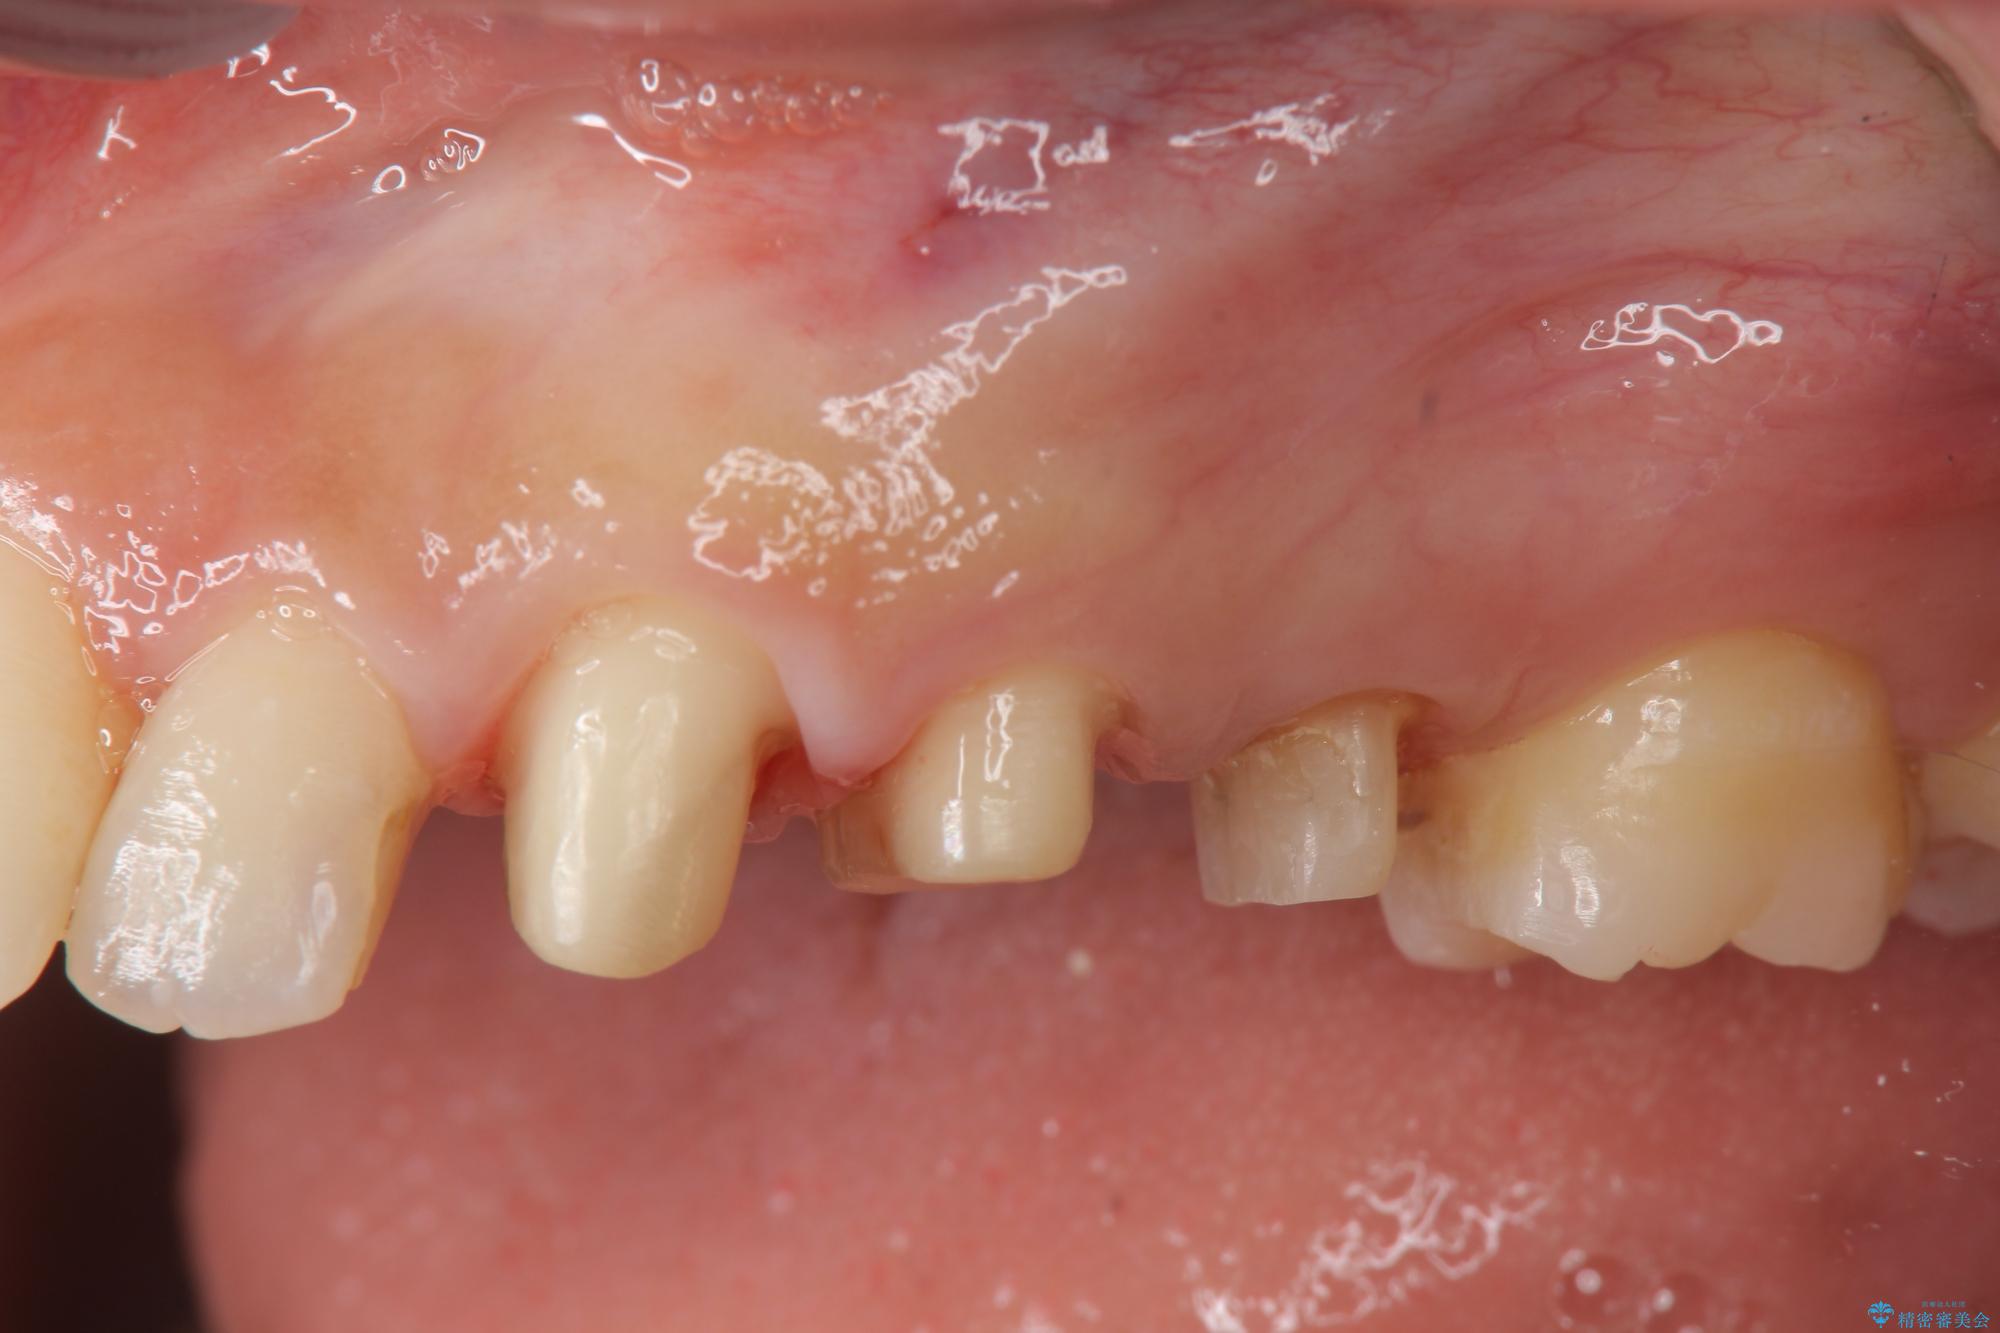

- 歯ぐきの腫れや、歯の内部が黒く見えることからの虫歯の治療を求めて来院されました。

虫歯が大きかったことから、神経の温存はできたものの歯ぐきよりも深い虫歯の問題を解決するため部分矯正治療を併用したセラミック治療を行うこととしました。

当初、歯ぐきよりも深い虫歯のぞんざいや、歯のポジションに問題がありましたがマルチブラケットを用いた部分矯正を行うことで適切な位置へと歯を移動させ、歯周環境を整えたセラミック治療を行うことができました。